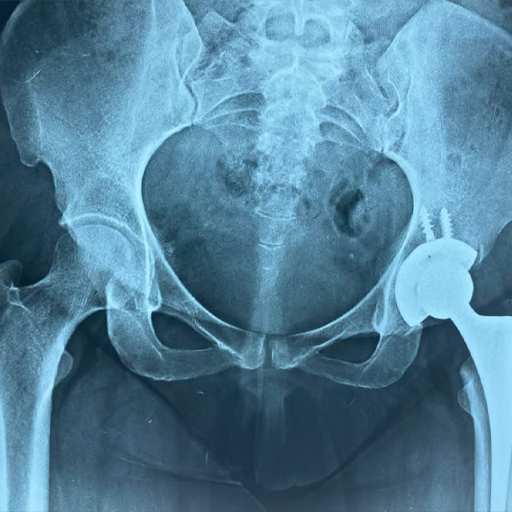

نماذج من حالات دكتور ساهر

يشتهر د. ساهر بمهارته الفائقة في علاج خشونة الركبة، وإجراء عمليات الرباط الصليبي وإصلاح قطع الغضروف الهلالي، إلى جانب تخصصه في تغيير مفصل الركبة والفخذ باستخدام أحدث التقنيات العالمية. بفضل اطلاعه المستمر على التطورات الطبية، يقدم د. ساهر كمال أحدث الحلول الجراحية لتغيير مفصل الفخذ، مع تحقيق نتائج استثنائية تضعه في مقدمة جراحي العظام على المستوى الدولي.